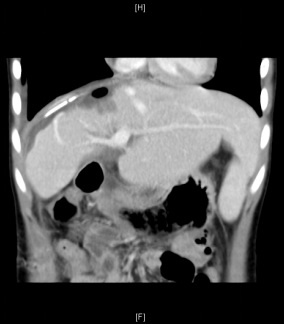

术前增强CT可见右肝巨大占位,约15x13x17cm,左肝推移,下腔静脉肝内段和中肝静脉受压,右肝静脉显示不清。